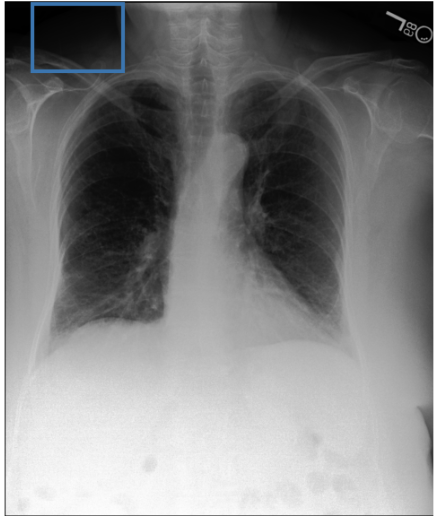

To address these drawbacks, state-of-the-art models such as MAIRA-2 [3] explicitly incorporate grounded report generation to better align local visual evidence with the textual findings. For example, MAIRA-2 is trained on a diverse set of localization-based tasks, including phrase grounding and grounded report generation. However, as shown in Figure 1, current models often exhibit a bias in which the target visual regions become overly associated with abnormal findings, leading to false positives in medical reports.

As shown in Table 1, our data composition reflects this imbalance: over 12.9M instances from Chest ImaGenome dominate the much smaller MS-CXR (815 PG instances) and PadChest-GR (12k instances) datasets. Beyond the imbalance between datasets, each dataset also exhibits substantial intra-dataset class imbalance. For example, anatomical regions in AGRG and semantic categories in PG are unevenly represented, leading the model to overfit frequent regions, neglect rare but clinically important ones, and hallucinate findings (Figure 1). Our curriculum framework addresses both sources of imbalance.